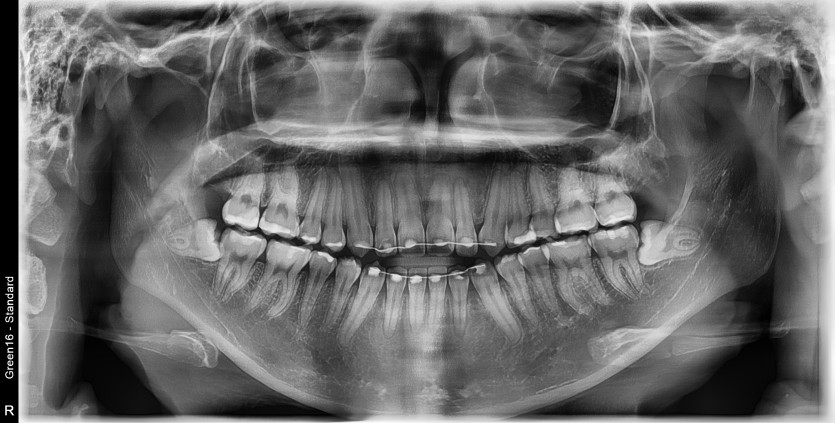

#38,48 사랑니 발치

구강 외과 전문의가 당일 발치했습니다.